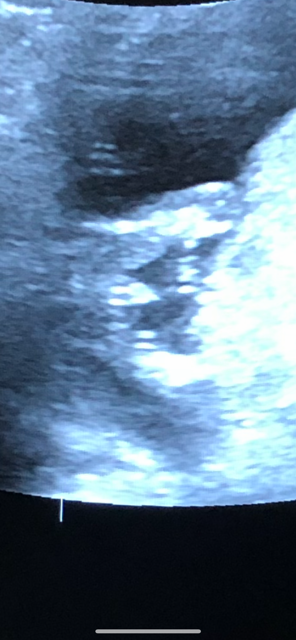

14 week scan

So, I had a ultrasound at 14 weeks. I’m 17+5 today and anxiously awaiting official 20 week scan Jan 2nd. What are your thoughts... boy or girl 💙💗. Tech says boy but I’m so worried it could be cord